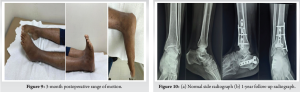

In the postoperative period, the left lower limb was kept elevated and, after swelling had reduced, a cast was applied. At the time of discharge, power of lower limbs improved to grade 3. Mobilization of the ankle and subtalar joints was initiated once the incisions had healed. The patient received physiotherapy treatment for 6 months. After discharge from the hospital, the patient was followed regularly for clinical and radiographic assessment in the outpatient clinic. The patient had good neurological recovery and regained bowel and bladder control. For the first 2 months, the patient was kept non-weight bearing on the right lower limb. He then gradually progressed to full weight bearing. 3 months postoperative, both fractures had gone on to unite clinically and radiologically. At final follow-up, after surgery, there was no radiographic evidence of posttraumatic osteoarthritis (Fig. 7).

Immediate post-operative shows acceptable Calcaneal height, but it is reduced later on which is common in comminuted calcaneal fracture.

The patient had terminal restriction of range of motion of both the ankle and the subtalar joints (Fig. 8 and 9).